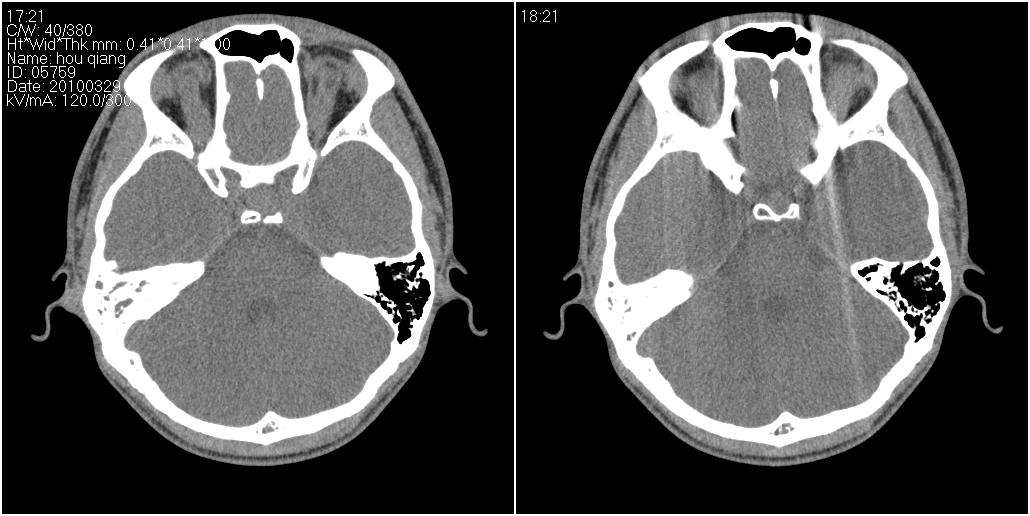

标题: CT25419:男性,18岁。右耳肿、痛5个多月。 [打印本页]

标题: CT25419:男性,18岁。右耳肿、痛5个多月。

右侧中耳乳突炎累及外耳道,鼻咽腺样体肥大。

1)右侧慢性中耳乳突炎并右侧中耳腔及外耳道肉芽肿或胆脂瘤形成。2)鼻咽腺样体肥大。